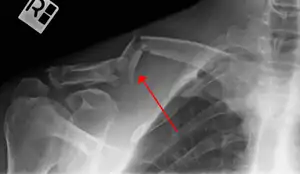

بجز معاینه بالینی، انجام پرتونگاری از محل شکستگی و ریه الزامی است و به ندرت نیاز به انجام سی تی اسکن و آنژیوگرافی لازم میآید.[1]